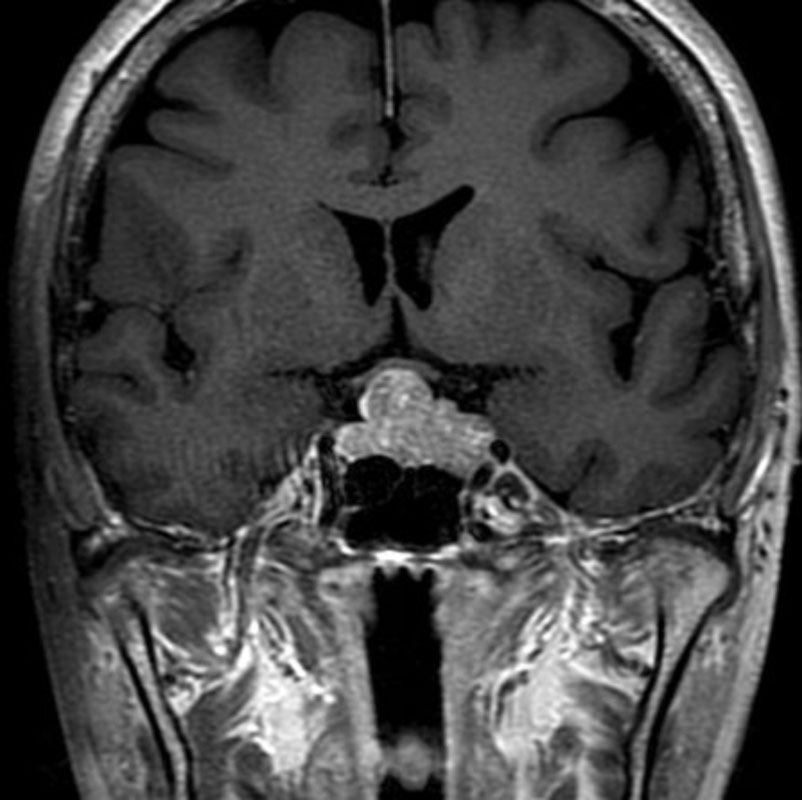

手術前1

手術前2